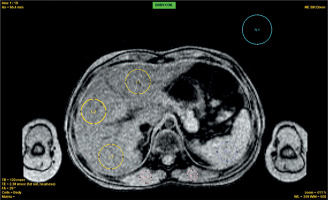

Figure 1

ROI placement for R2* analysis Axial ME-GRE image showing ROIs for liver (L1-L3, yellow), spleen (S1, blue), muscle (M1-M2, red), and background noise (N1, cyan). ROIs were selected to avoid vessels and organ boundaries. Acquisition: TR = 120 ms, TE = 2.38 ms, FA = 20°